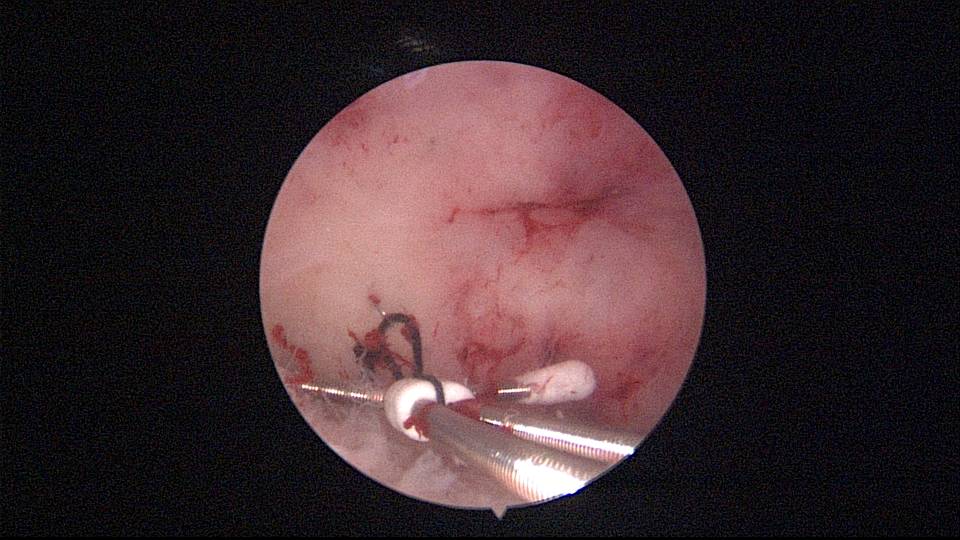

患者42岁,G6P2,剖宫产2次。2025年2月,停经48天,计划外妊娠,要求终止妊娠并放置节育环,考虑终止妊娠后宫腔大,担心环移位或脱落,要求固定节育环。γ环没有尾丝,用4号丝线连接环及不锈钢挂钩,将挂钩插入宫底肌层固定节育环。异物钳夹持挂钩送入宫腔可能在宫颈管皱襞上受阻,可以用中弯钳将挂钩送入宫腔下段,然后异物钳夹持挂钩插入宫底肌层。2025年3月复查B超,节育环位置正常,环顶端距宫底1.8cm。